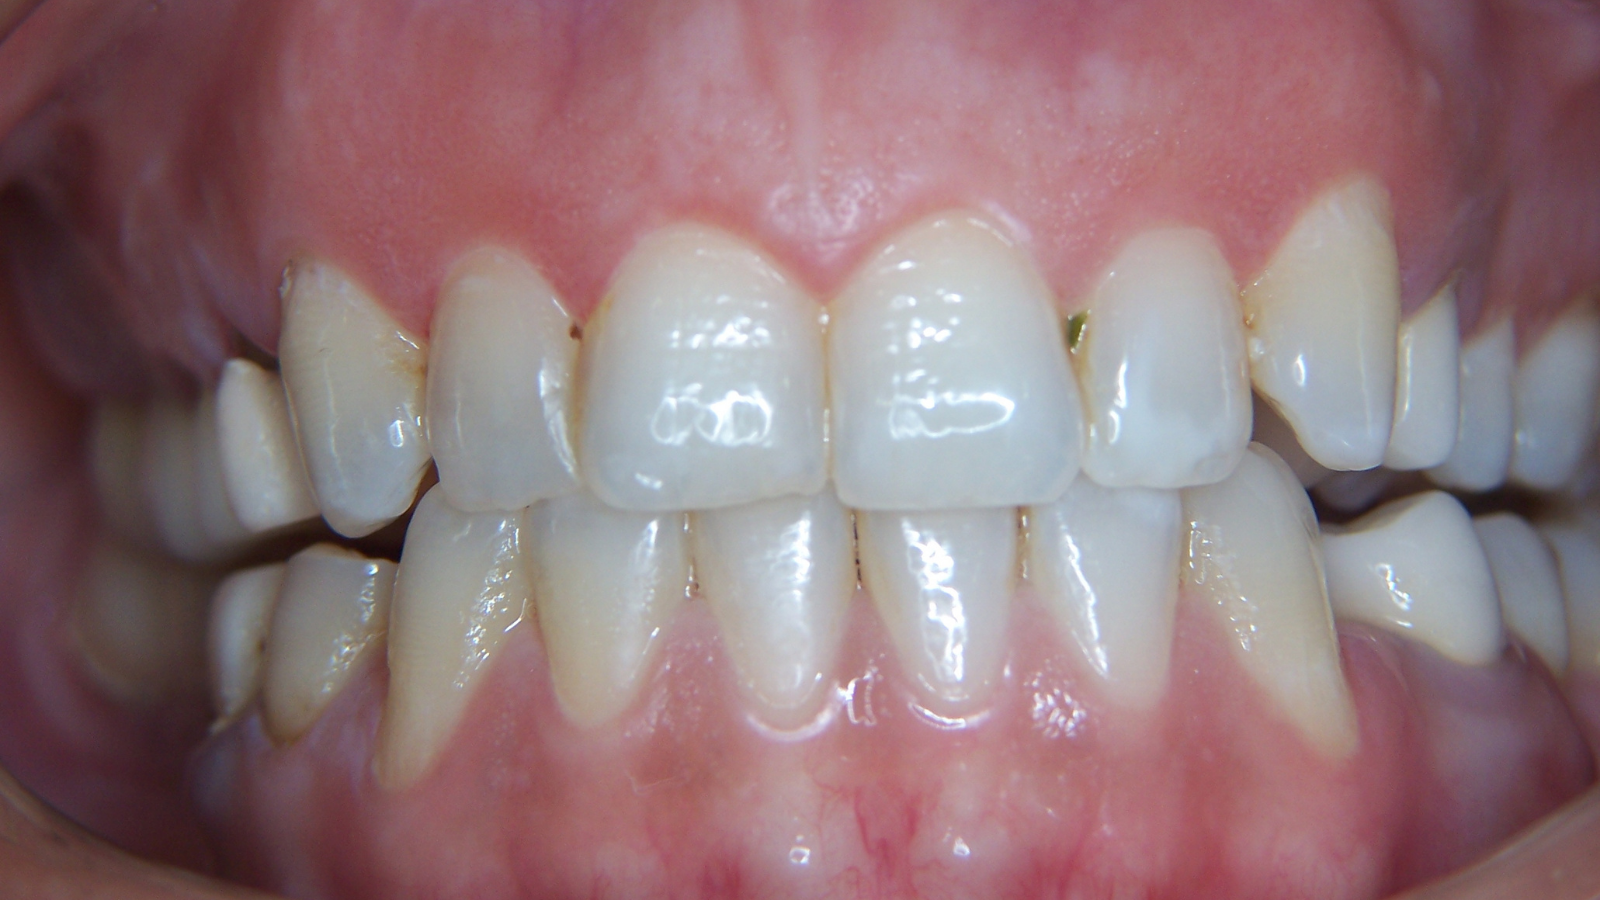

Facettes de canine à canine : sourire plus harmonieux et naturel

Un patient se présente pour rendre son sourire plus harmonieux. Les images “Avant” montrent un secteur antérieur avec une esthétique perfectible, notamment au niveau de l’homogénéité, des contours et du rendu de surface.

La prise en charge a consisté en des facettes de canine à canine, avec un objectif clair : retrouver un résultat naturel avec de la brillance, du relief et de la translucidité.

Les images “Après” mettent en évidence un sourire plus équilibré, avec une meilleure continuité entre les dents, un rendu plus lumineux et une texture plus réaliste.

Images :